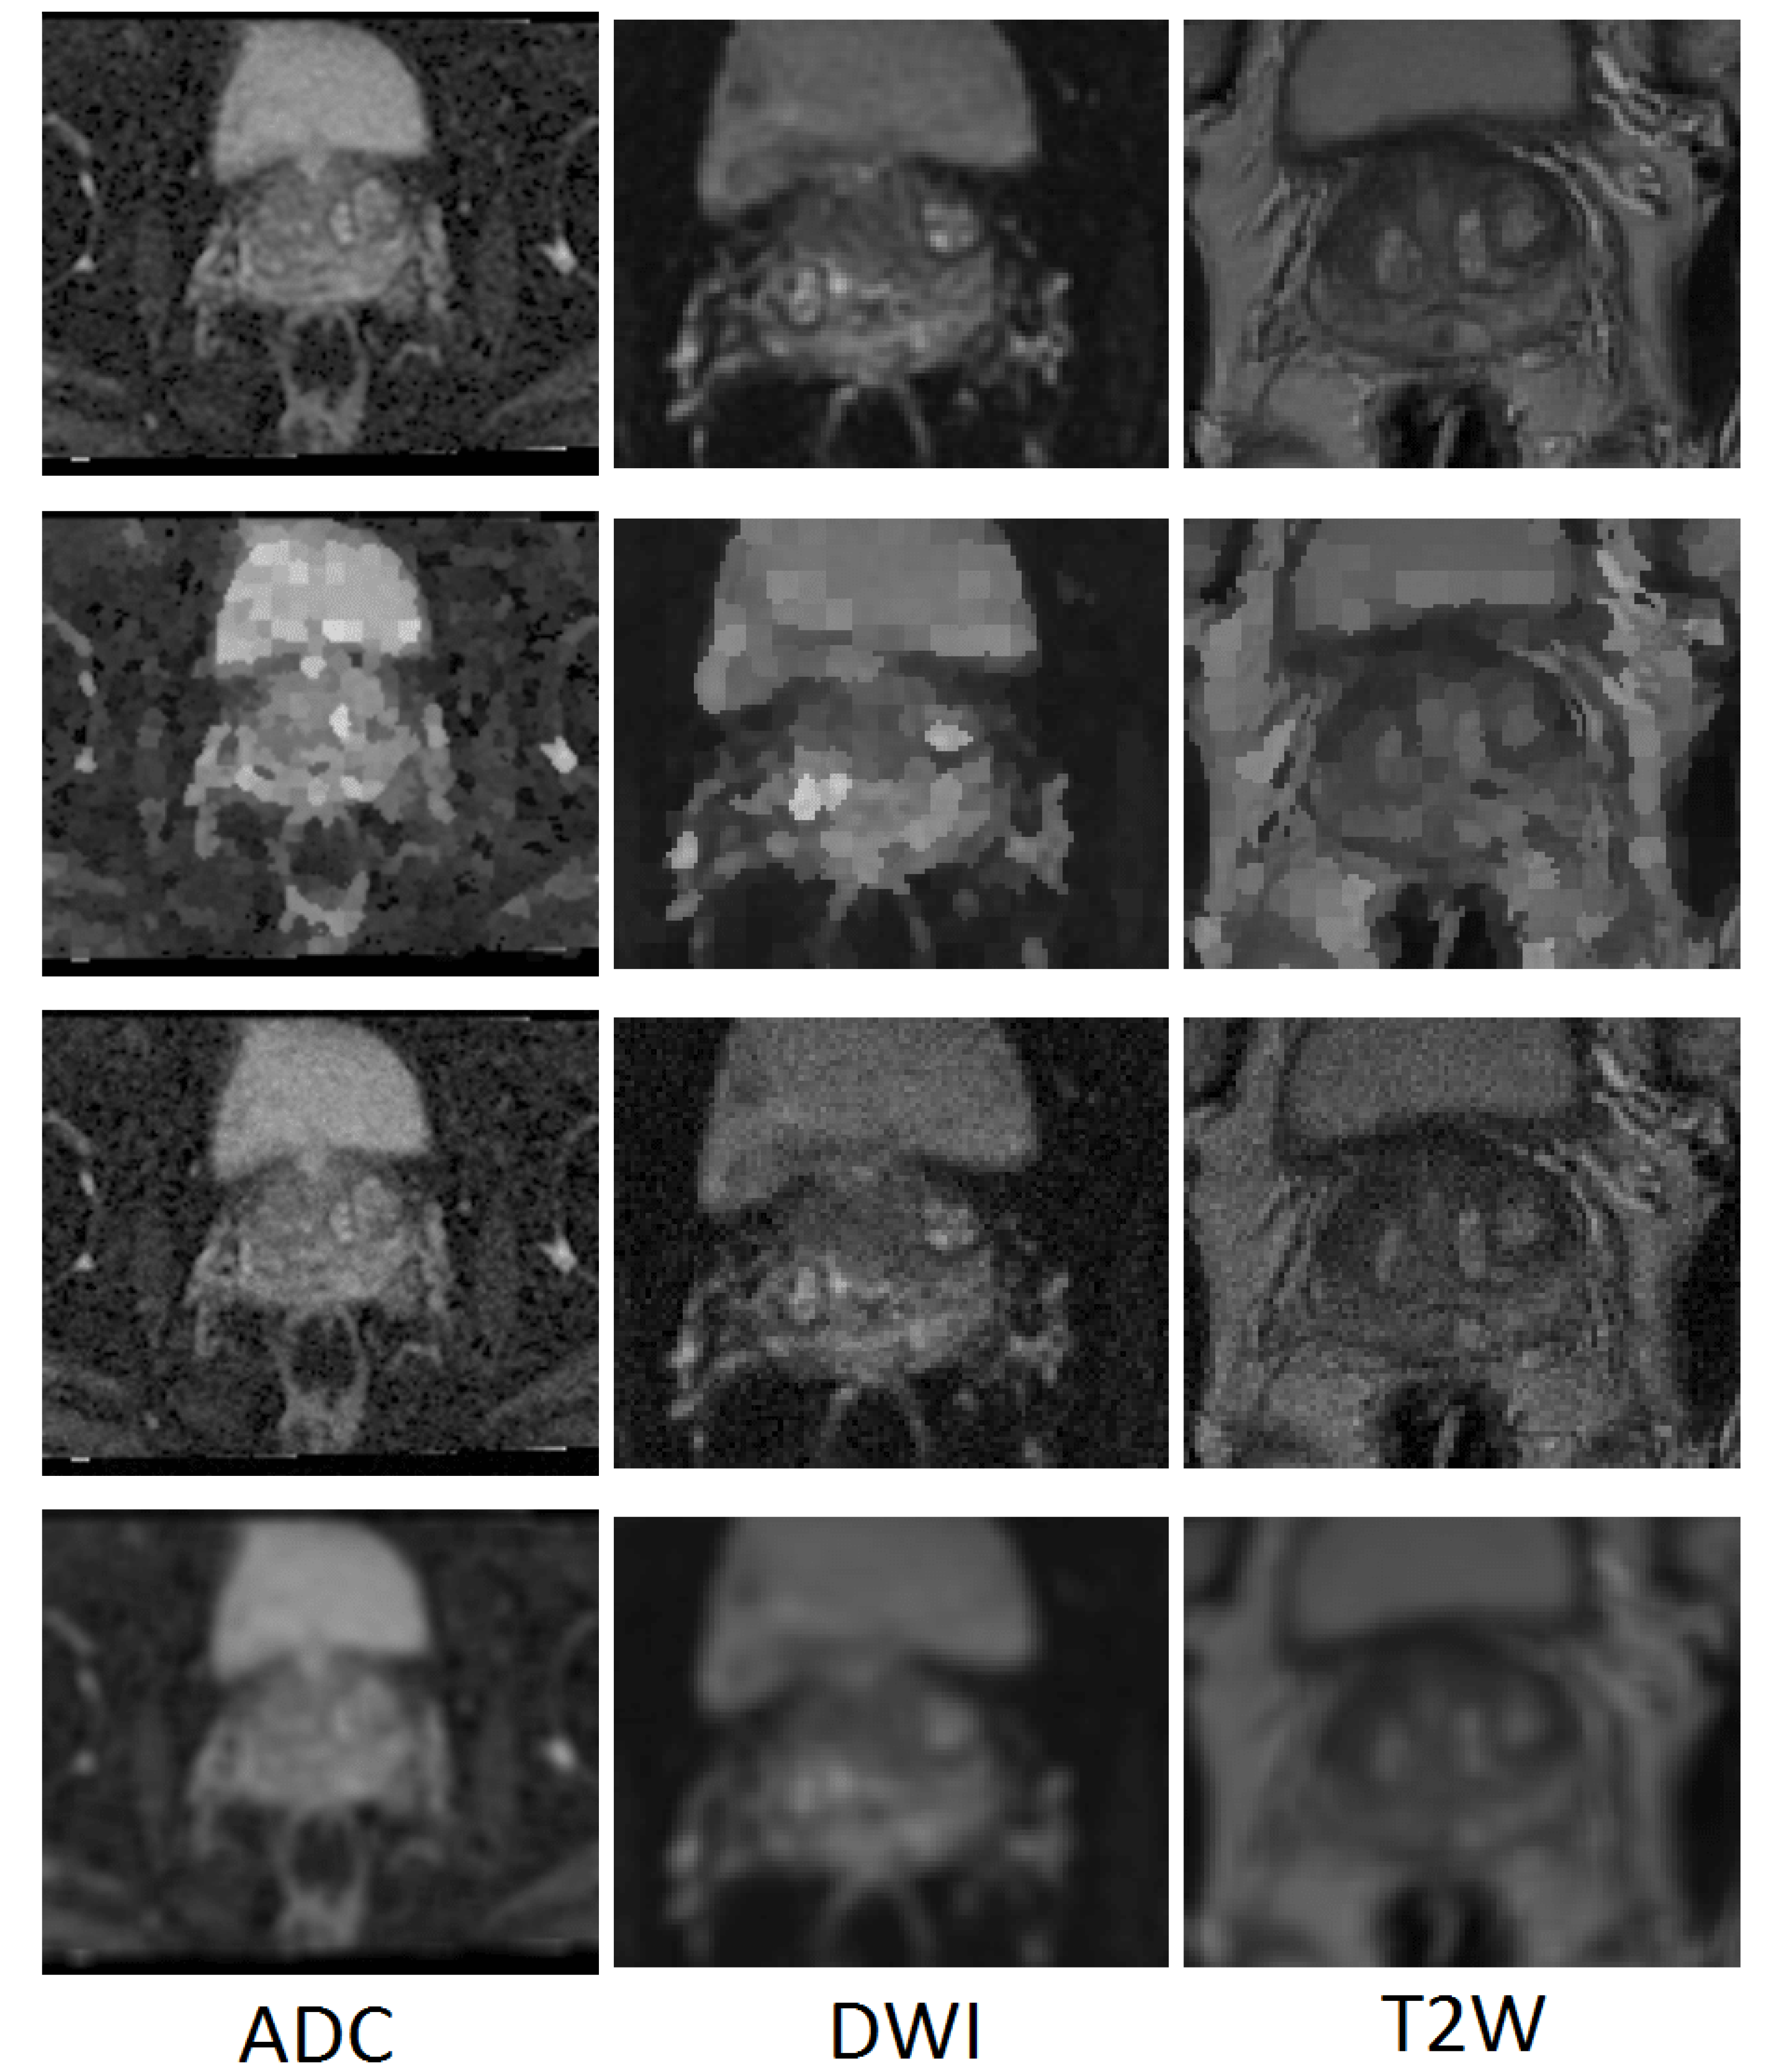

In order to examine the generalisability of the models on another representative set of MR images acquired in a clinical setting, the publicly available dataset (PROMISE12) [25] was used. This dataset contains 50 cases including T2-weighted MR images of the prostate. This dataset is multi-center and multi-vendor and has different acquisition protocols, with various prostate sizes and appearances. Details of the acquisition protocols for the different centers is explained by Litjens et al. [25]. Due to different MRI protocols (e.g., differences in slice thickness, magnet strength, with/without endorectal coil), the quality of the images was different in this cohort. Figure 2 shows some slices from different data cohorts to show appearance differences. There is a spread in prostate sizes and appearance in all images in our clinical cohort and the public dataset.

Figure 2.

Some slices from different data cohorts to show appearance differences with T2 modality. First row: PROMISE12 dataset. Second row: our clinically collected dataset.